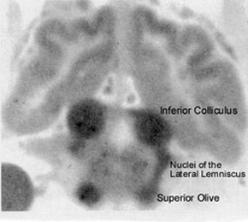

From: Kety SS (1962) Regional

neurochemistry and its application to brain

function. In French, JD, ed, Frontiers in Brain

Research. New York: Columbia University

Press, pp 97-120.